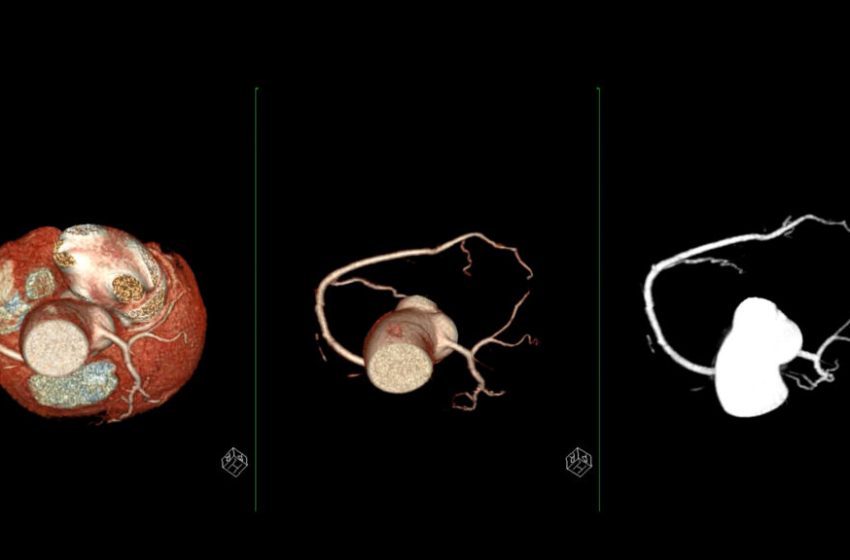

The latest example of important sex differences centers on the plaque burden in coronary arteries — a measure of fat and cholesterol deposits that also accounts for blood vessel size.

Women tend to have lower volumes of plaque than men, but their total plaque burden is higher because the fatty deposits take up a larger fraction of their smaller coronary arteries. Their risk for a heart attack or hospitalization for chest pain emerged when their plaque burden was lower than men’s, and their risk climbed more steeply, too, a new study published Monday in Circulation: Cardiovascular Imaging concluded.

The observational study looked at the coronary CT angiography scans (or CCTA) of just over 4,200 people — half women over age 50 and half men over age 45 — who made up a subset of the much larger PROMISE trial, a study of adults with stable chest pain and no history of coronary artery disease. The new analysis revealed that fewer women (55%) than men (75%) had any coronary plaque; the women also had smaller amounts.

Even so, women were just as likely as men to die from any cause over the two years they were followed. Most striking for researchers hoping to understand whether plaque carries the same prognostic meaning in women and men, the women’s heart risk rose when they had less plaque compared to men. The women’s risk of heart attack or chest pain that would send them to a hospital started at a 20% plaque burden, compared to men’s risk starting at 28%. As plaque levels climbed, risk rose more sharply for women than for men.

Just as it has been more common to measure the quantity of plaque rather than the burden of plaque in small arteries, most studies and clinical practice have focused on the obstructive plaque that, as its name suggests, blocks coronary arteries. Women are more commonly diagnosed with non-obstructive coronary artery disease than men. Despite sounding less threatening, non-obstructive heart disease is still serious: the heart’s arteries tighten, function poorly after branching into tiny vessels, or get squeezed by heart muscle.